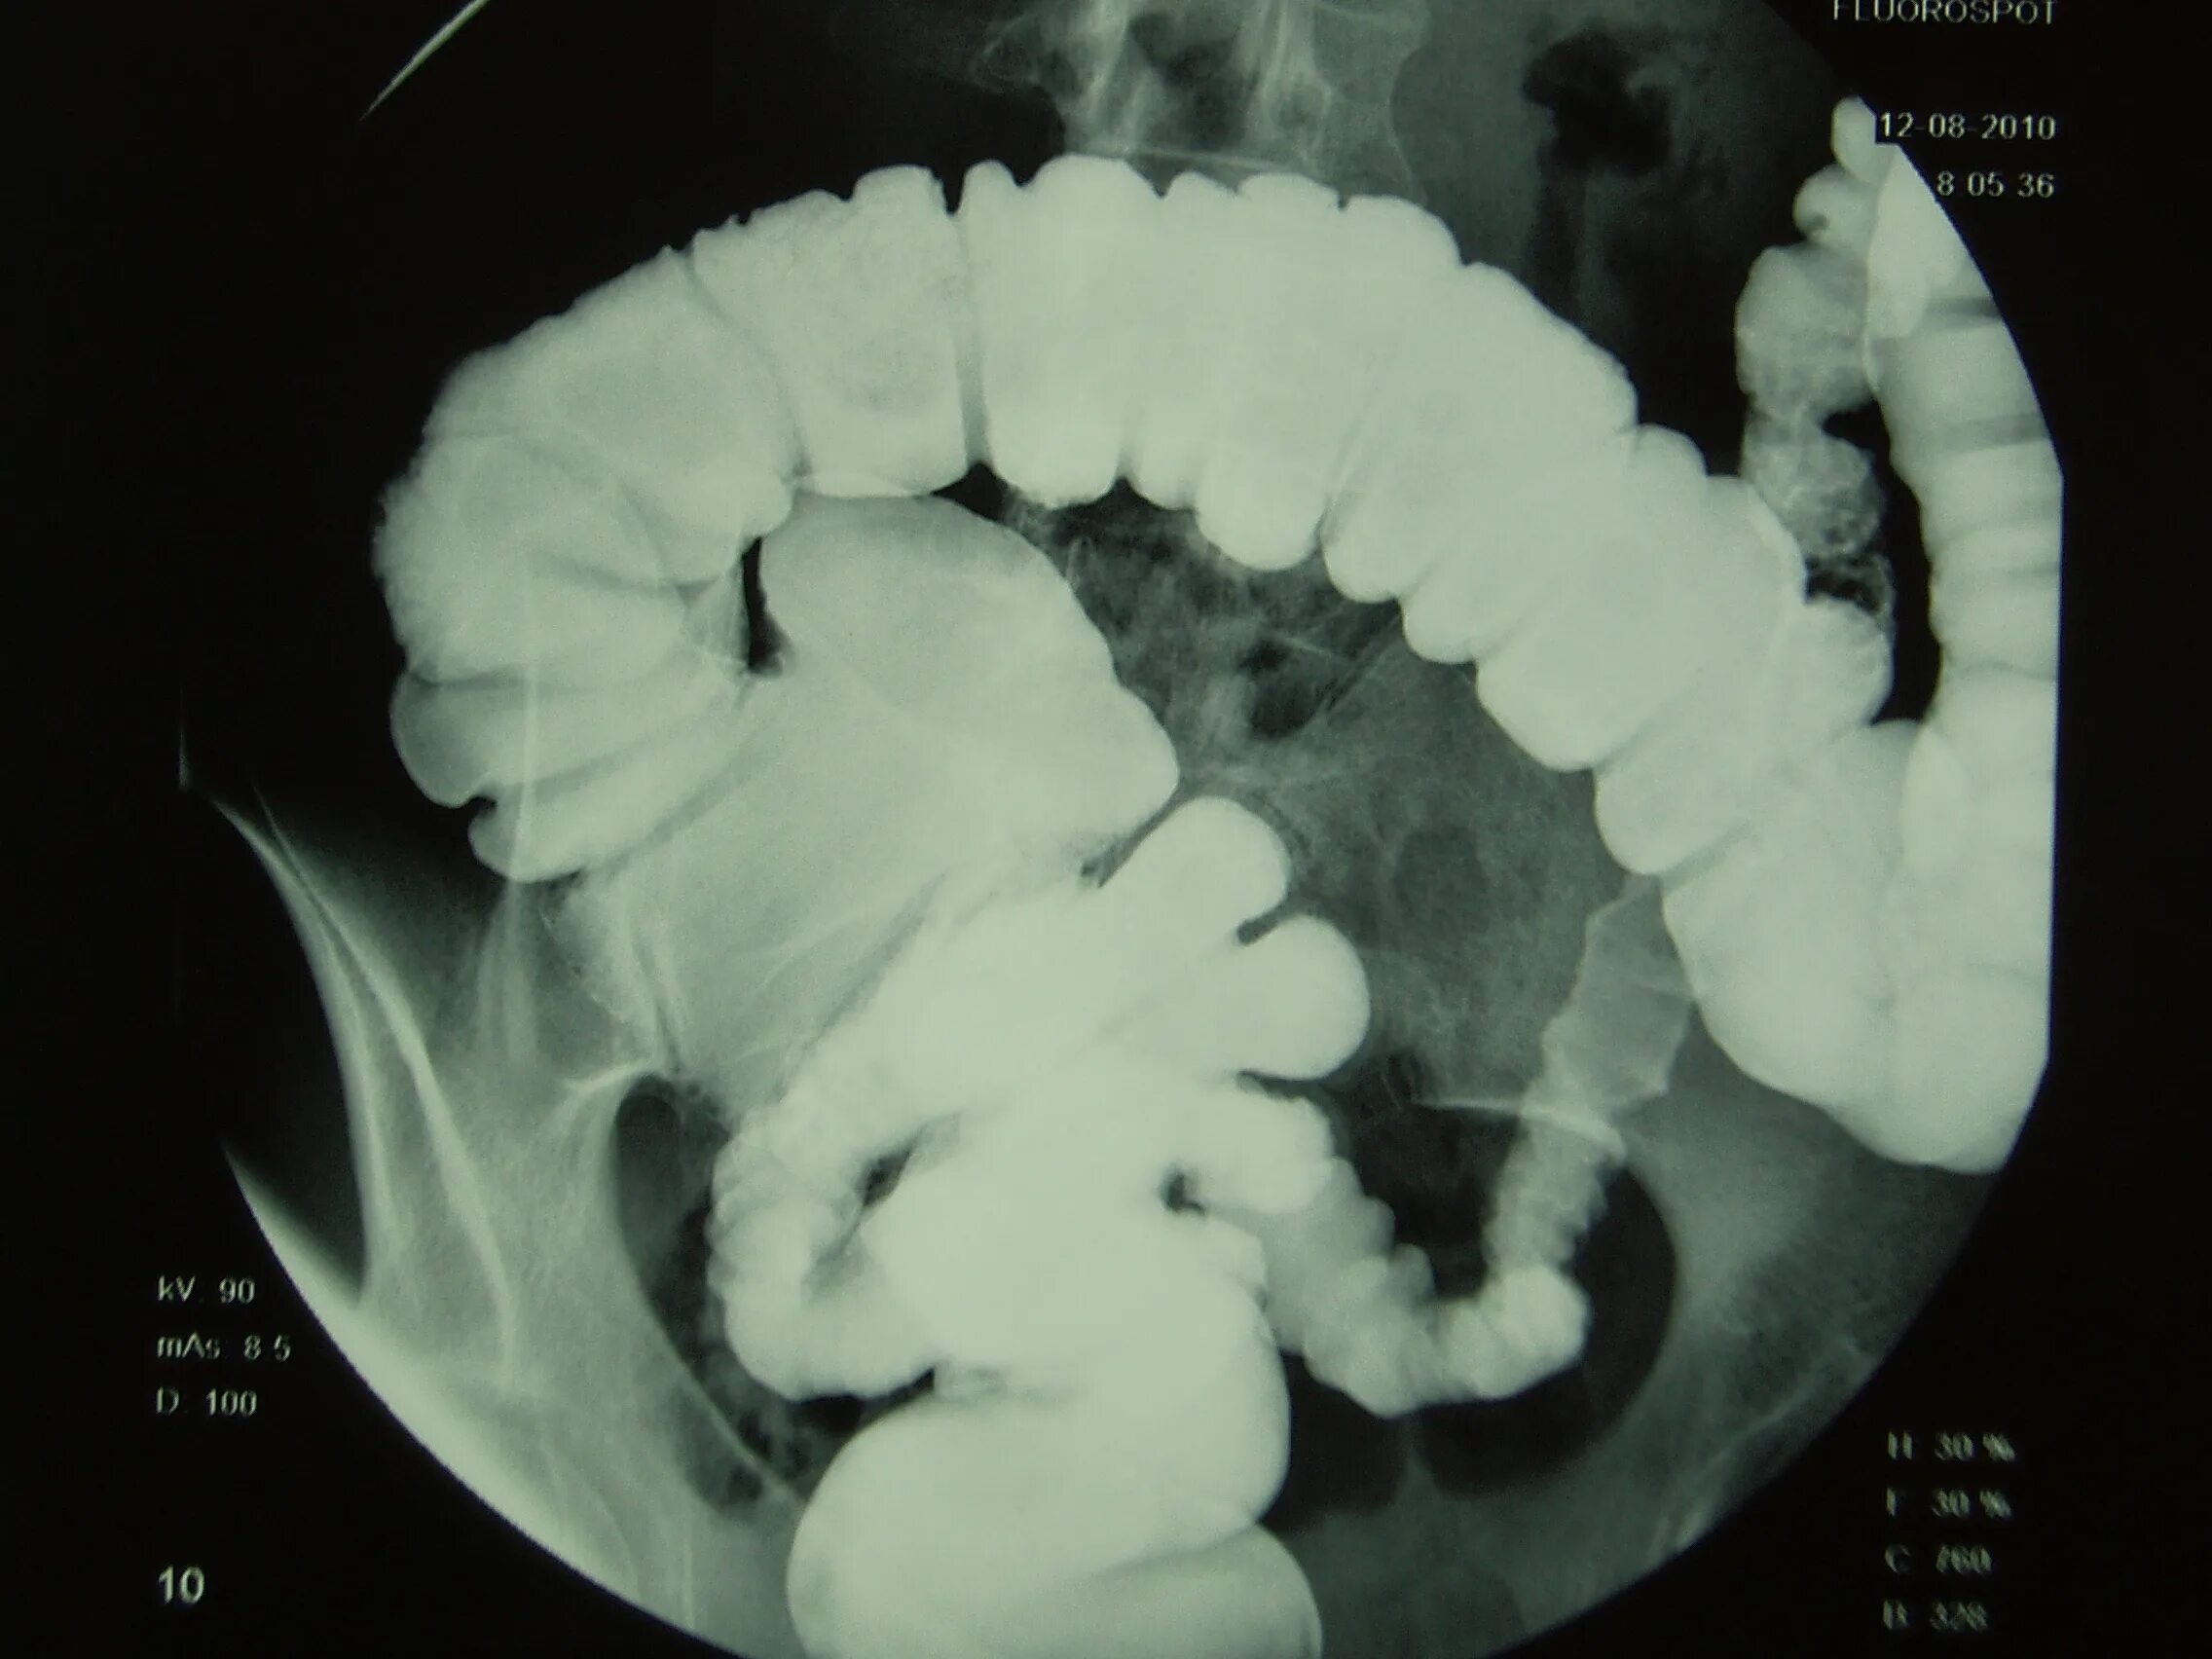

Долихоколон симптомы у взрослых